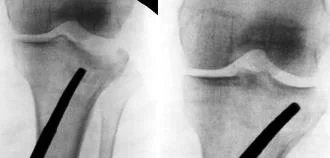

Law of Two’s

- Plain x-ray: (law of two s)

- Two views: AP and Lateral

- Two joints: joint above and joint below

- To show other injuries

- To assess rotation

- Two limbs: for comparison

- more in children to compare epiphysis

- Two occasions

- e.g. stress fractures

- e.g. scaphoid fracture

- Two injuries

- e.g. patellar fracture and hip injury

- e.g. calcaneal fractures & spine injuries

- …and two Doctors!!